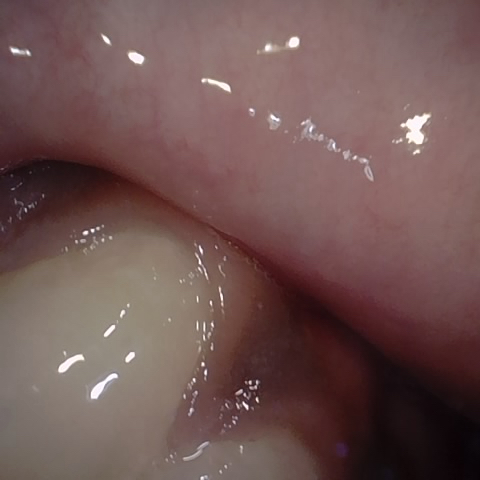

Annotated as "Bad"